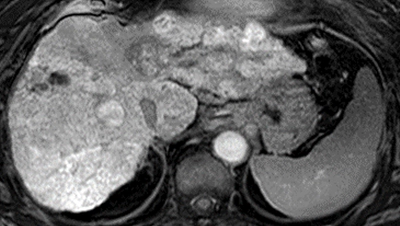

肝細胞がん免疫療法の効果を予測する画像バイオマーカーを発見 免疫療法の効果がない患者に対するMRI診断の有効性を証明

世界初!免疫チェックポイント阻害剤の有効性を事前予測 個々の患者に適した肝がん薬物治療法の確立に期待